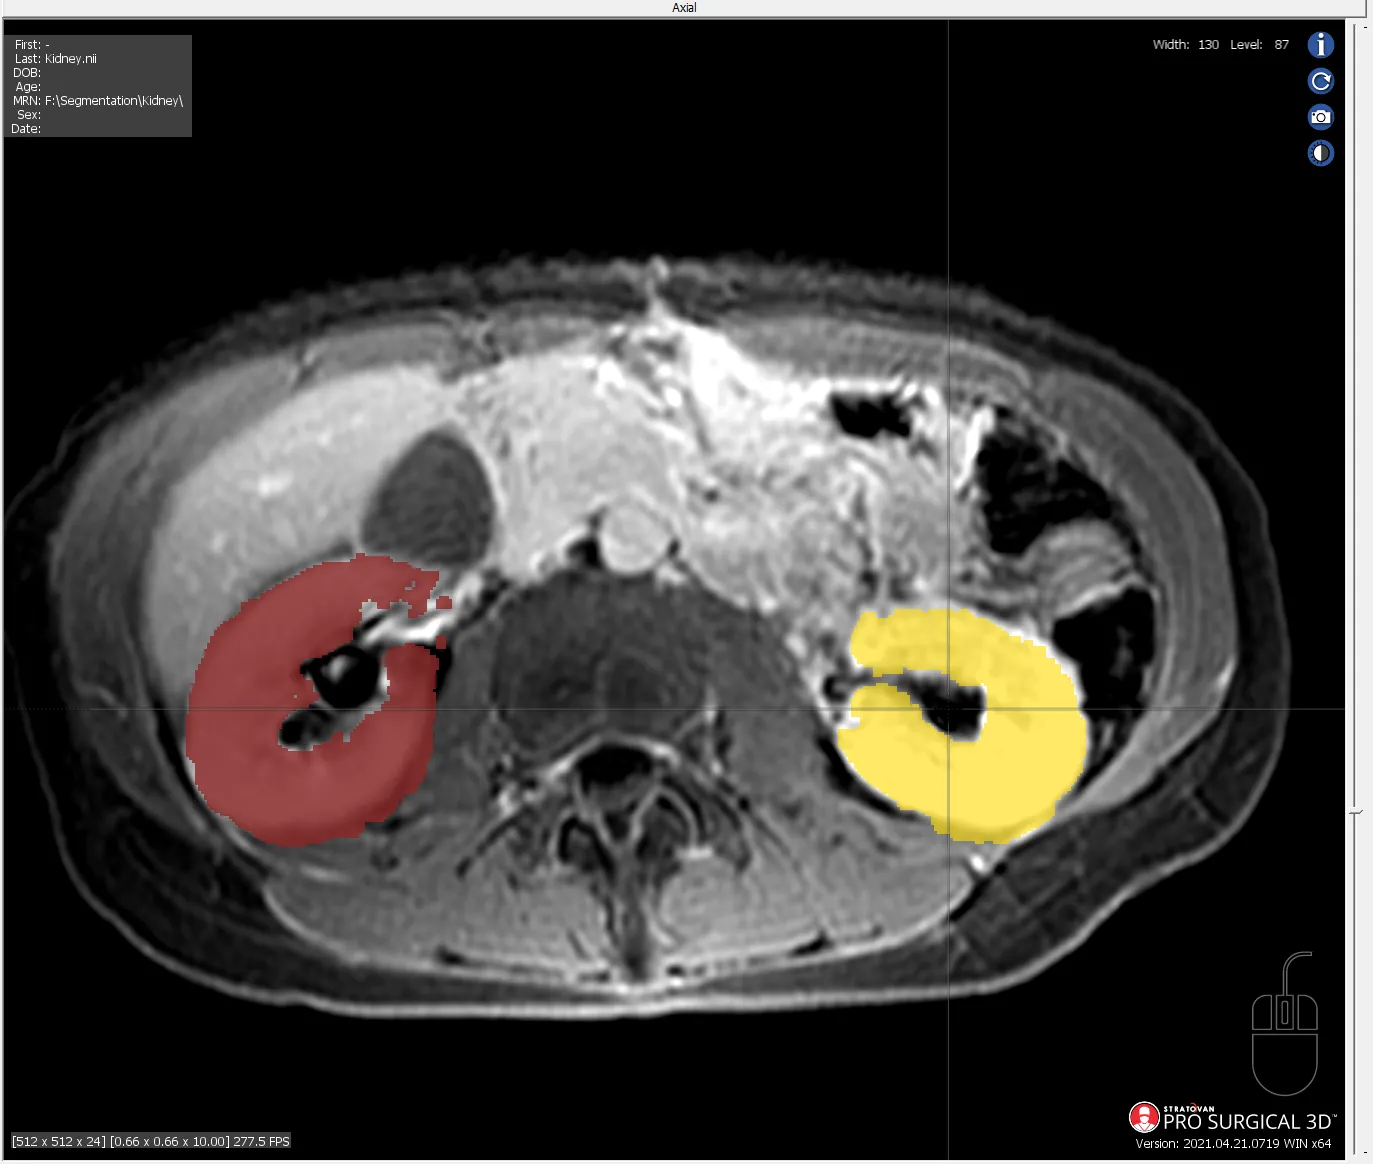

MRI segmentation of human brain ventricle

Quality assurance review of the AMOS 2022 Grand Challenge data